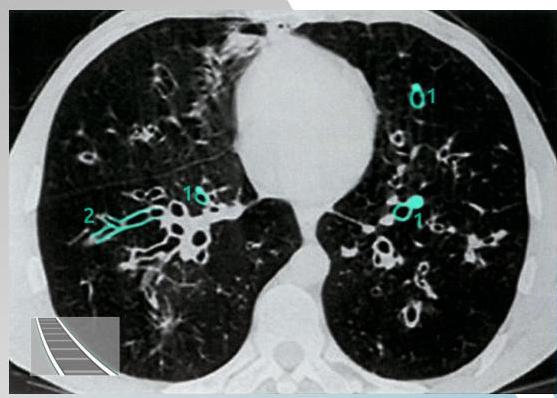

- ☐ Thin-section HRCT scanning: is the gold standard, with excellent sensitivity and specificity.

CT Scan Findings

Cylindrical

Saccular/Varicoid

Cystic